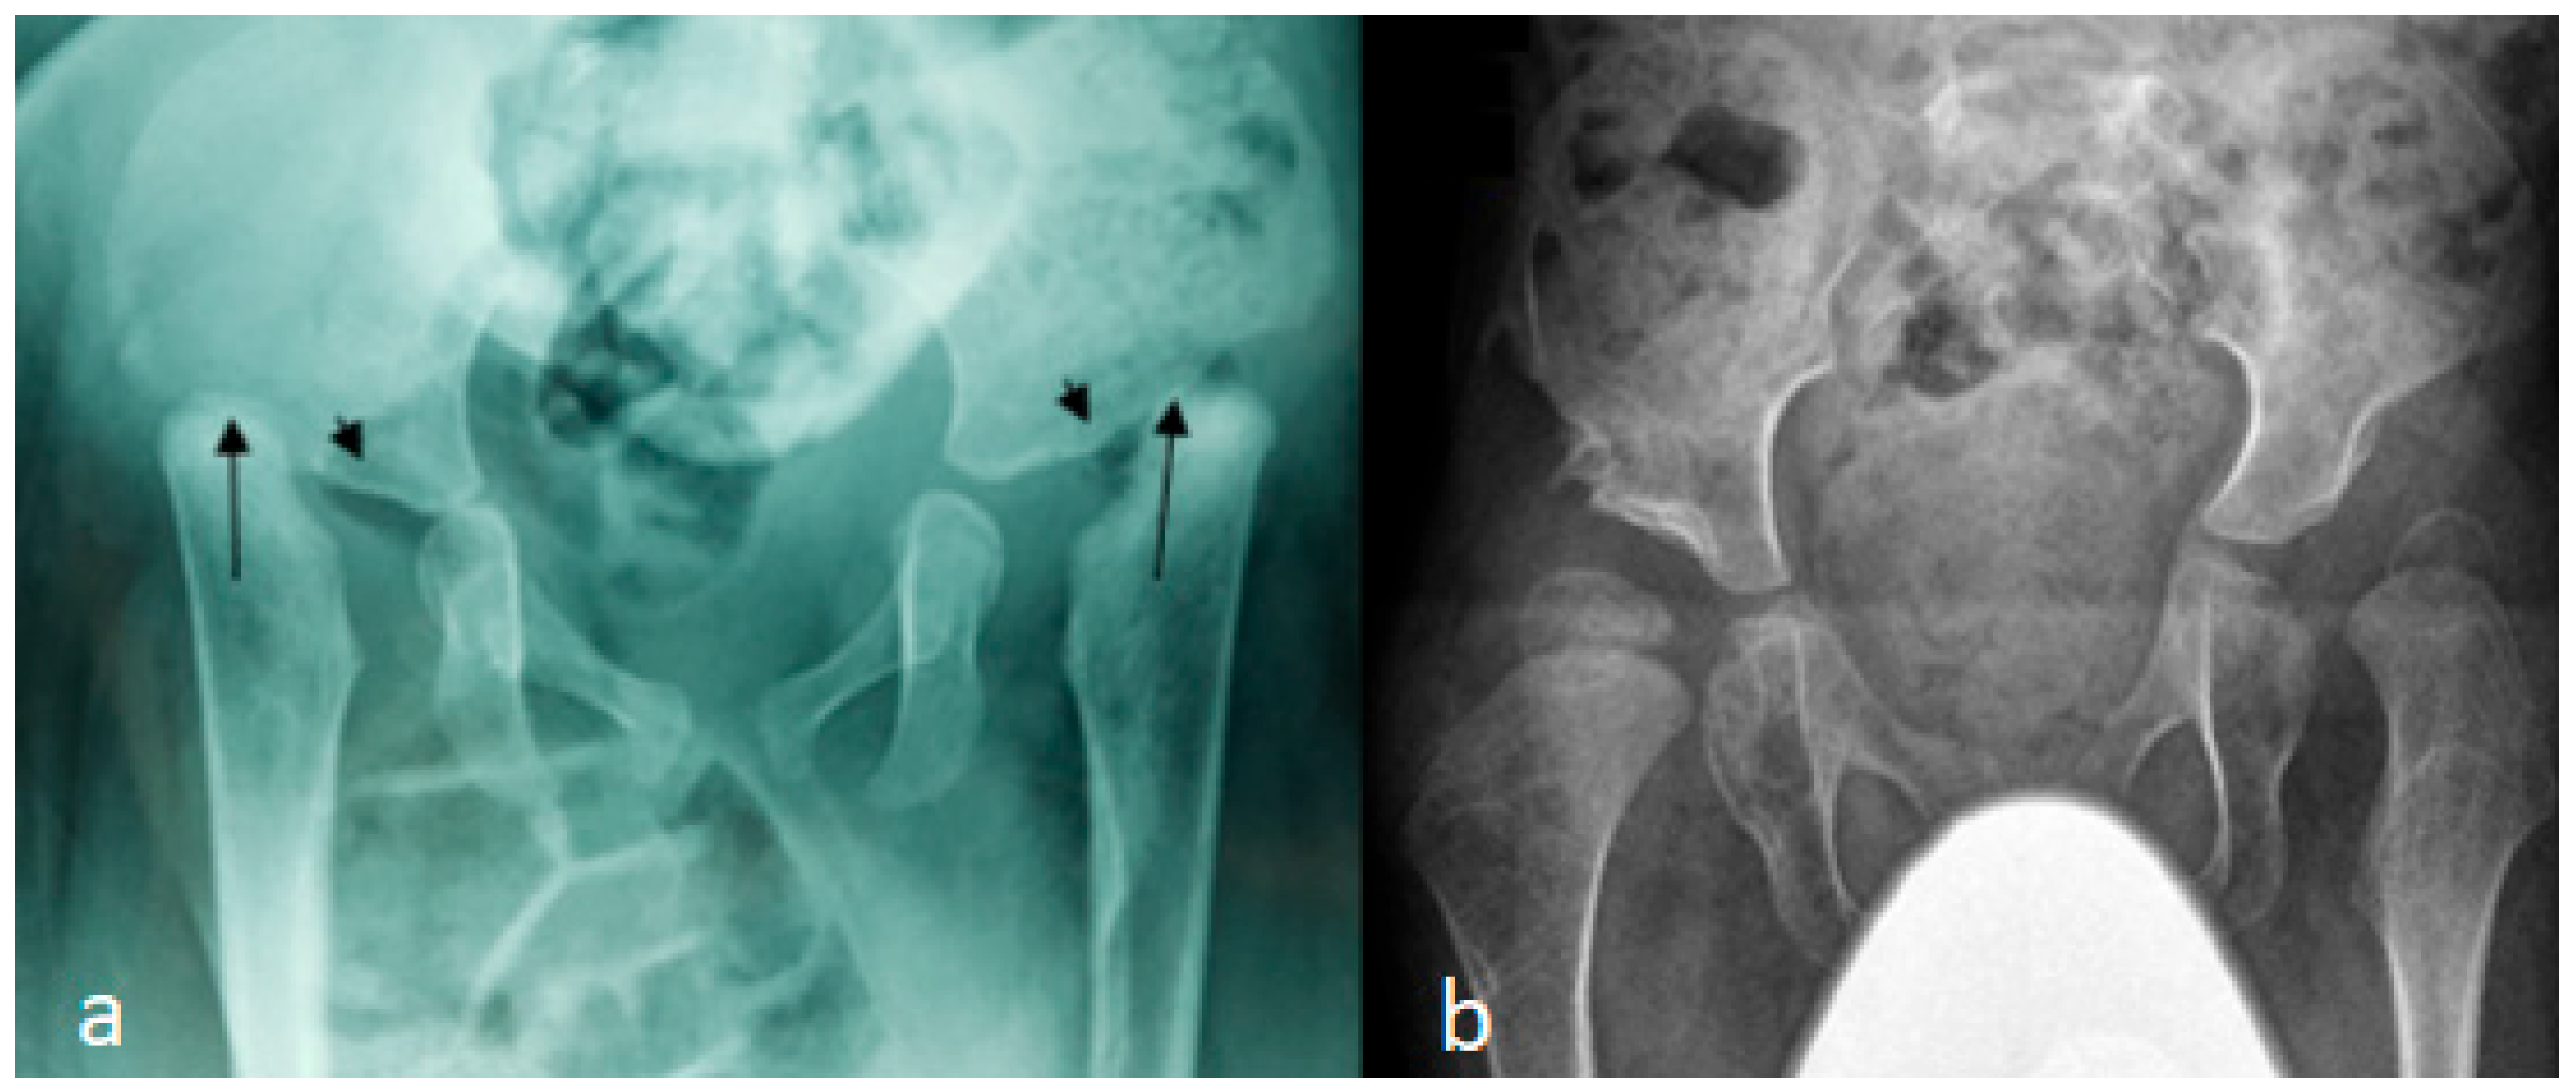

In these children, dysmorphic facial features were evident, which encompassed distinctive facial features, frontal bossing, and a flattened nasal bridge giving the facial phenotype of a dish-like facies. Our orthopedic strategy is based upon detailed clinical and radiological phenotypic characterization. Radiological phenotypic interpretations have been organized for all children by referring to 3D CT scan. In a lateral skull radiograph of a 7-month-old boy with Larsen syndrome, one can note brachycephaly, frontal bossing, and marked disproportionate small facial bones in comparison with a large cranium and dysplastic cervical spine, osteopenia of the lambdoid bones causing downward bulging, and prominence of the occipital bone associated with progressive thinning of the squamous part of the occipital bone (arrow). One can also note the cervical kyphosis (arrow) AP hand radiograph of a 3-year-old boy with Larsen syndrome showing retarded bone age, expansion of the distal ends of the shortened metacarpals, a thumb proximally placed, and the presence of accessory bone adjacent to the distal third metacarpal-phalangeal bone (arrow). One can also see the delta phalanx of the middle metacarpophalangeal bone of the fifth finger (arrow) (b) (Figure 1a,b). The AP pelvis radiograph of a 7-month-old girl with Larsen syndrome showed bilateral hip dislocation associated with maldevelopment of a severely dysplastic acetabulum and dysplastic capital femoral epiphysis (a). The AP pelvis radiograph of a 3-year-old boy with Larsen syndrome showed bilateral hip dislocations (severe acetabulo-femoral dysplasia) (Figure 2a). The AP pelvis radiograph of a 7-month-old girl with Larsen syndrome showed bilateral hip dislocation associated with maldevelopment of a severely dysplastic acetabulum and dysplastic capital femoral epiphysis (a). The AP pelvis radiograph of a 3-year-old boy with Larsen syndrome showed bilateral hip dislocations (severe acetabulo-femoral dysplasia) (Figure 2b). AP knees radiograph of a 5-month-old boy with Larsen syndrome showing bilateral knee dislocations (arrows) associated with under tubulation of the tibae and fibulae. Note the fragmented/deformed epiphyses and that the right tibia is medially subluxated. Note bilateral talipes equinivarus associated with double ossifications of the calcaneus (arrows) (Figure 3).

Figure 2.

(a,b): AP pelvis radiograph of a 7-month-old girl with Larsen syndrome showing bilateral hip dislocation associated with maldevelopment of severely dysplastic acetabulum and dysplastic capital femoral epiphysis (arrows) (a). AP pelvis radiograph of a 3-year-old boy with Larsen syndrome showing bilateral hip dislocations (severe acetabulo-femoral dysplasia) (b).